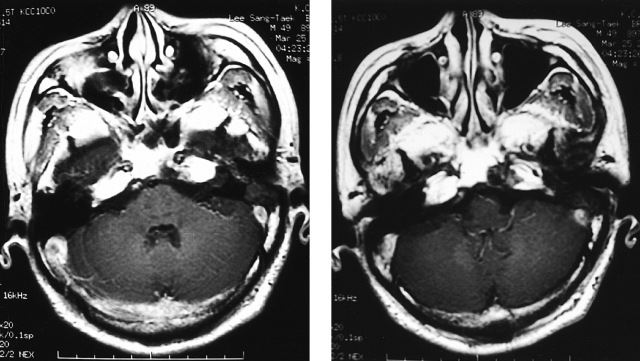

Figure 1

Brain MRI. T-1 weighted image showed tumor thrombosis involving the superior sagittal sinus, straight sinus, transverse sinus, and sigmoid sinus.